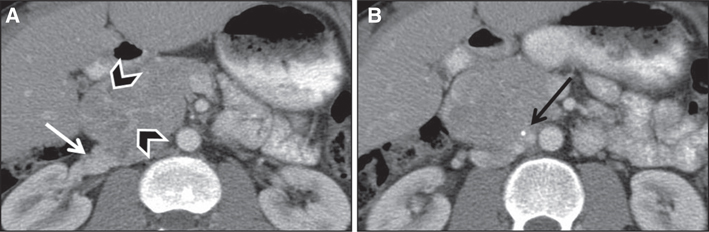

Fig 7

Figure 7 A 65-year-old male patient with right middle ear cavity mass. (A) In-111 pentetreotide whole body planar and (B) lateral spot images of the head performed 24 h after administration of radiotracer show moderate focal tracer uptake in the region of the right middle ear. (C) T1-weighted fat-suppressed post-contrast coronal brain MRI shows an avidly enhancing mass in the right jugular foramen concerning for a glomus tumor. Surgical pathology showed a 1.2 cm × 0.6 cm × 0.3 cm lesion with positivity for synaptophysin and chromogranin on immunohistochemistry, compatible with a paraganglioma.